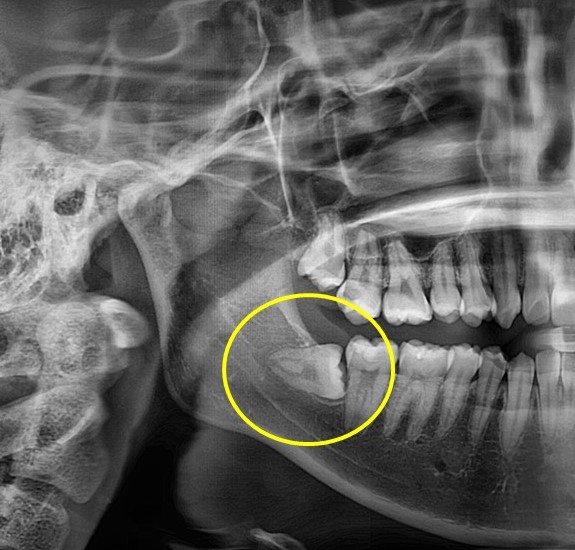

수술 전

수술 후

매복사랑니 발치사례

전후사진